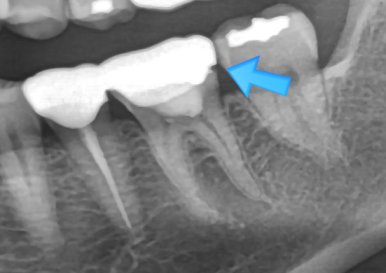

정밀 검진 결과,

하악 어금니(#36, #46) 부위에서

보철 경계의 착색과 미세 틈이 관찰되었습니다.

보철 내부 우식 의심도 있었기에

기존 금니를 제거하고 내부를 확인했습니다.

- #46: 기존 보철 제거 시 아말감 코어 확인 → 내부 충치 확인

- #36: 보철 하부에서 크랙 라인 확인